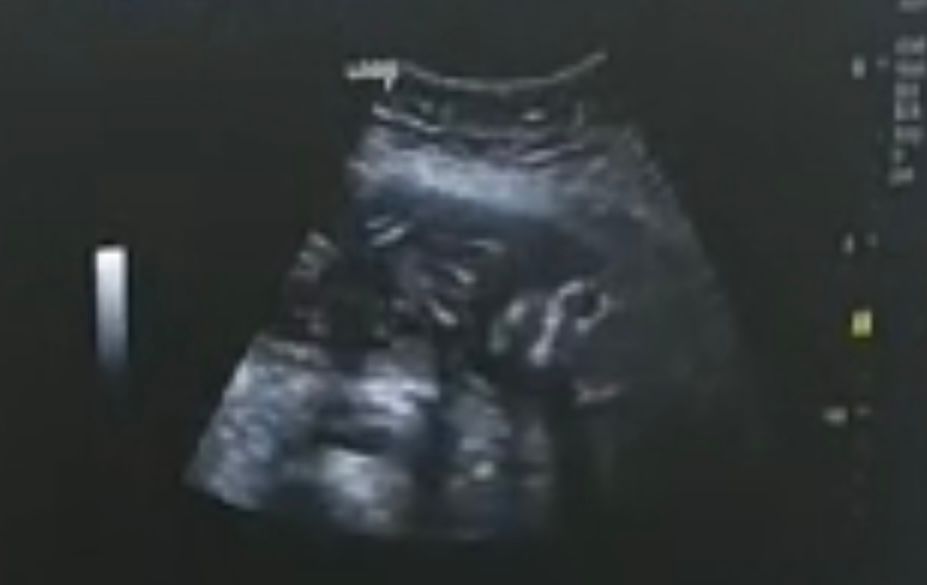

Camy, я была на платном скрининге) сказали, что уперся попой в матку и ноги скрестил) через месяц думаю сделать еще узи, чтобы пол узнать

Узи 11,5 неделек 2 скрининг